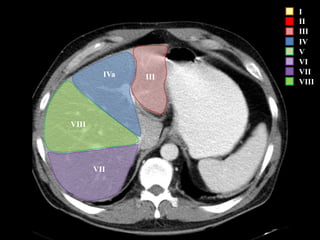

I – Entre cava y porta

II – el más superior de los izquierdos

III – Por debajo del II

IV – por delante de la vesícula

V – por detrás de la vesícula

VI – relación con riñón derecho

VII – el más posterior de los segmentos superiores

VIII – domo hepático

Las claves de la segm. Hepática